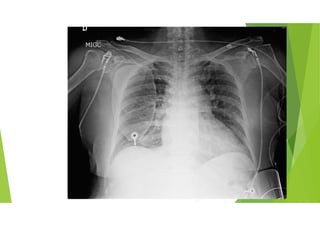

Caso Nro 2: Varón 46a... 4 días más tarde...

En URGA normoTA, taquicárdico, con semiología clínico-radiológica de IC

en RS con BRIHH , con troponina I no elevada.

EF: TA 103/77 mmHg , FC 85 lpm, satO2 96%. TCR sin soplos

signficativos. Galope por 3r ruido. MVC con crepitantes bibasales. IY +.

ECG: ritmo sinusal a 120 lpm, eje -30º, Crecimiento AI. PR normal,

BCRIHH 130ms

Hemograma normal con Hb 14.5g/dl. Coagulación normal con dímero D

442ng/ml. Cr 1.34 (previo 1,27 mg/dL), ionogrma norma. Troponina I

US 18,1 ng/L. PCR 10,8.

Buena evolución inicial en planta bajo tratamiento deplectivo.

ECG al alta RS 80lpm.